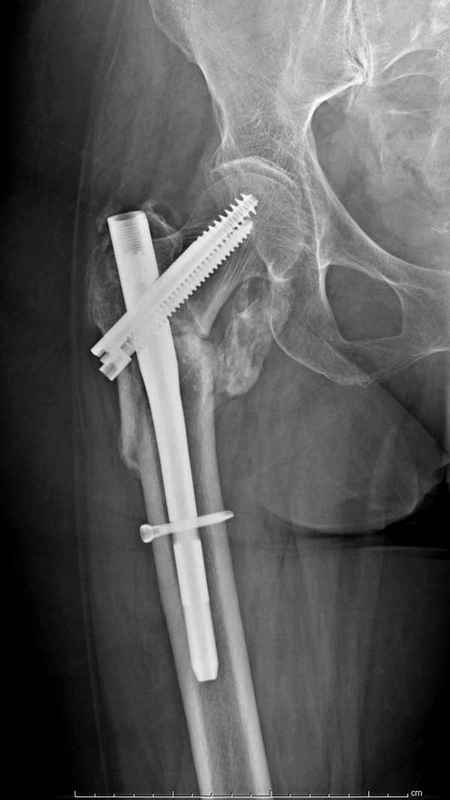

Здесь пара случаев фиксации похожих переломов:

первый высокоэнергетическая травма 36 лет